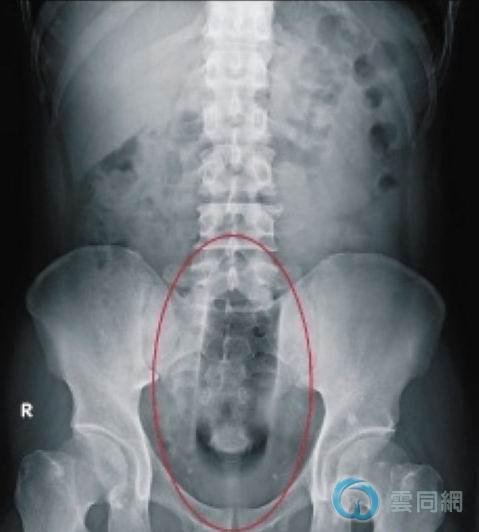

36岁吴姓男子疑因自慰,将长17公分的化妆瓶塞进肛门,拔不出来,忍痛从新竹一路开车返回中县大甲,经李综合医院外科医师麻醉后,将患者送进开刀房以胆囊夹夹出瓶子,幸男子仅肛门轻微出血裂伤,目前已出院。

吴男一进急诊室,医师检查发现整个瓶子已没入肠中,由於瓶子又滑又硬,根本夹不出来,赶紧将患者送进开刀房,经麻醉后以手推肚,将瓶子推到肛门口,再利用夹胆囊的大钢牙镜夹将瓶子取出,前后共花了40分钟才完成。